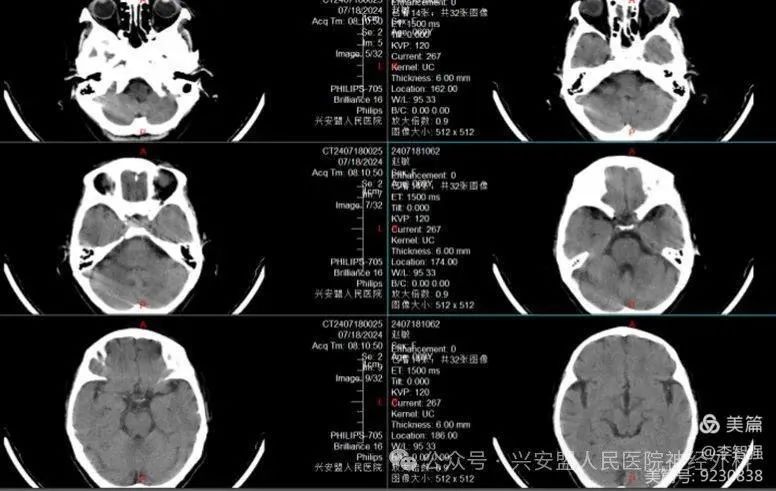

近几个月来,69岁的赵阿姨,因为这个“小东西”吃了不少苦。反复的头晕、头痛以及视力减退使得她来到兴安盟人民医院神经外科就诊。门诊完善头颅CT、头颅核磁,提示:颅内鞍区占位,考虑垂体瘤,且她的蝶骨非常厚,属于复杂的甲介型鞍底,甲介型鞍底因先天蝶骨没有气化成窦腔,解剖标志难以识别,手术很难采用经鼻蝶微创治疗。

头颅核磁及头颅CT骨窗可见气化不良的甲介型鞍底